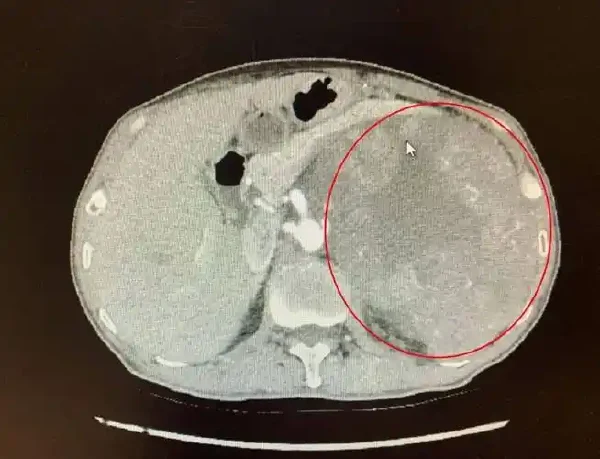

在提供的病例中,盆腔右侧壁见软组织团块影,边界欠清,大小约3.4×3.1cm,这可能提示腹膜后区域存在肿瘤。影像报告如此描述,CT影像和增强扫描显示肿块不均匀强化,提示内部结构复杂,有血供丰富的可能性。